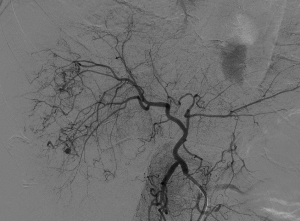

入院后,为患者给予补液,在局部麻醉下行DSA引导下经导管肝肿瘤动脉栓塞术。

肝癌破裂大出血并失血性休克患者往往病情急、危、重,如果治疗不及时可能短期内死亡。未开展介入治疗的医院对此类患者只能给予输血,补液,急诊手术,在插管全麻下行开腹手术治疗。但开腹手术往往切口长、手术时间长、手术创伤大,麻醉副作用大。可能术后出现肝功能衰竭,再出血,腹腔感染,切口疼痛,切口感染等并发症。介入手术则往往较少出现这些并发症。介入手术只需要在腹股沟穿刺一个2mm的小孔,置入导管到肝动脉,注入栓塞剂栓塞肝肿瘤的动脉,手术创伤小,止血可靠,除肝区疼痛及发热外,较少出现其它并发症,病人舒适度明显提高,而且能早期进食及下地活动,恢复快,能缩短住院时间,具有疗效好且微创的优点。